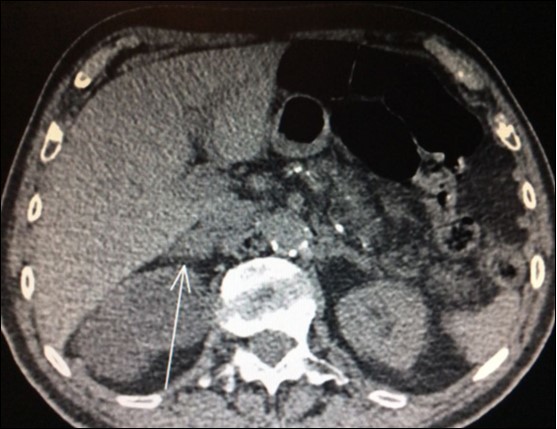

Usually, the imaging screening used for diagnosis of adrenal metastasis are: CT scans (Figure 1), magnetic resonance imaging (MRI) and PET-CT. The sensitivity of PET-CT has conflicting results, being of 96% and with false-positive detection rate even for smaller masses (without swelling and not evident on CT or MRI) of only 4% as reported in some series8,9,18. Another study confirms these findings, showing sensitivity and specificity of PET/CT for distant metastasis of 94% and 85%, respectively31.

Figure 1.CT scan showing isolated right adrenal NSLC metastasis (Arrow)

CT scan showing isolated right adrenal NSLC metastasis (Arrow)